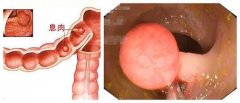

肠息肉怎么治疗?

导语 盘锦医生表示:肠息肉是指肠黏膜表面突出的异常生长的组织,在没有确